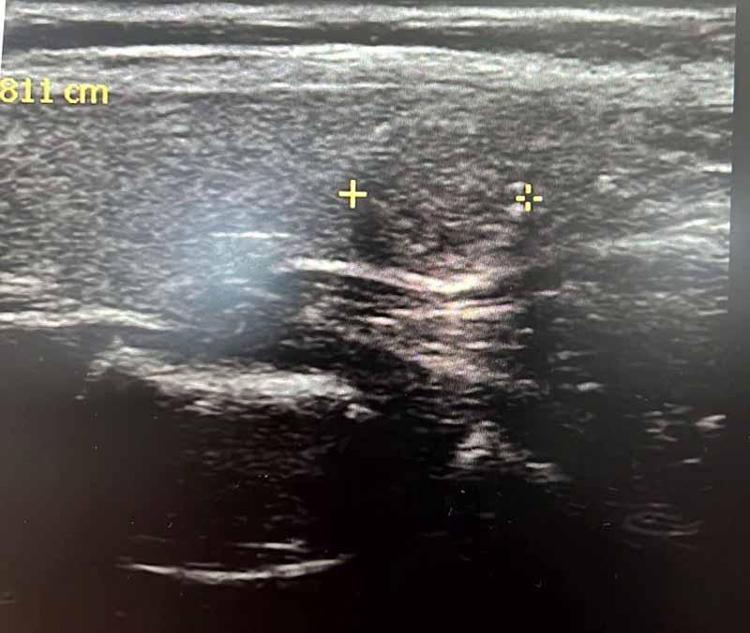

Tiroit nodülü tespitinde farkındalığın artığını ifade eden Dr. Demir, "Nodül tespitindeki farkındalığımız arttı. Tiroit ultrasonu kullanıyor olmamız da bu artışa etken oldu. 'Bası bulgusu' ile dokunarak muayene ettiğimizde; mevcut olan nodüllerin yaklaşık yüzde 20’sini tespit edebiliyoruz. Nodüllerin birçoğunun özelliklerini ve boyutlarını ise tiroit ultrasonu ile tespit ediyoruz. Son dönemlerde vakalarda artış var.

Bazen hiçbir semptomu olmayan hastalarda da tiroit nodülleri tespit ediyoruz. Nodülleri özelliklerine göre değerlendirerek gerekli hastalardan biyopsi alıyoruz. İyi ya kötü huylu nodüle göre tedavi uyguluyoruz. Nodülü belli aralıklarla takip ediyoruz. Tiroit nodüllerinin yüzde 10 ila 20 kadarı kötü huylu olabiliyor. Birçok kanser türü erkek hastalarda fazla görülürken, özellikle tiroit kanseri sıklığı kadın hastalarımızda daha yüksektir. Kadın hastalar daha sık muayeneye geliyor ve farkındalıkları daha yüksek" diye konuştu.